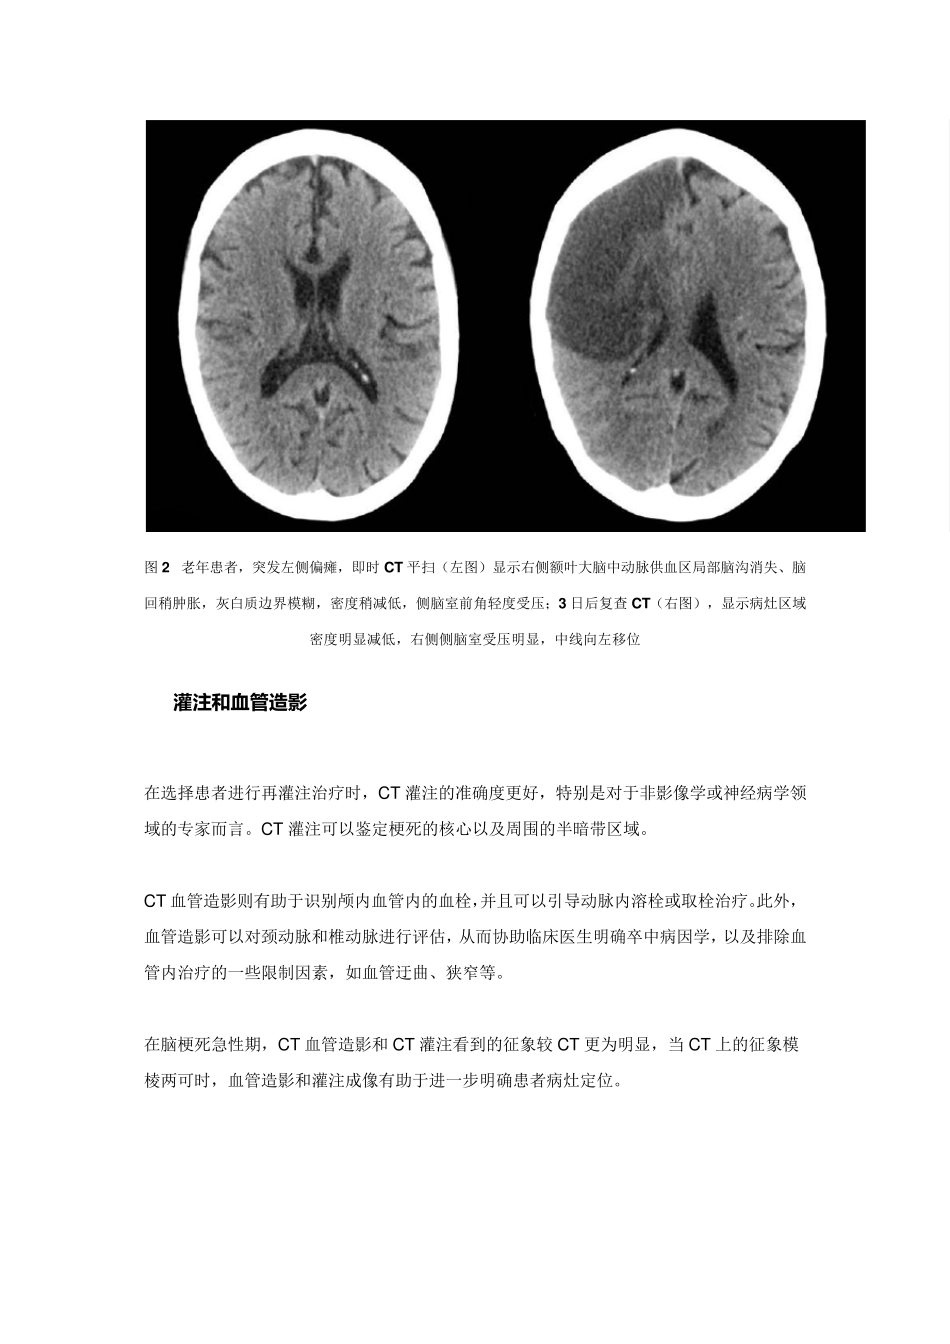

看 图 说 话 : 缺 血 性 脑 卒 中超急性 期的影像学特点 导读:对于疑为缺血性脑卒中的患者而言,CT是临床上首选的辅助检查,CT灌注、MRI等技术的应用更是为缺血性脑卒中的早期诊治提供了莫大帮助。本文将结合影像学资料,对缺血性脑卒中超急性期的影像学特点进行梳理。 典型的缺血性脑卒中表现可分为超急性期、急性期、亚急性期和慢性期。临床上,人们通常将发病 6 小时之内的缺血性脑卒中病例归为超急性期,一些影像学文献则将 12 小时之内的病例也包括在内。在超急性期对患者进行快速识别,排除非缺血性脑卒中神经系统疾病,并明确梗死区域,有助于尽早确定下一步的治疗方案。 CT 作为一种急症,缺血性脑卒中的诊治需要争分夺秒。头部 CT 平扫方便快捷,是急性脑卒中患者的首选,然而在缺血性脑卒中的早期,CT 的灵敏度有限。急诊 CT 的主要目标是: ➤ 排除颅内出血,以确定患者是否可以溶栓治疗; ➤ 寻找任何早期脑梗死的特征改变; ➤ 排除类似脑卒中的其他颅内病变,例如肿瘤。 超急性期时,CT 上脑实质并不会出现非常明显的密度改变,但超急性期的几个征象对于早期诊断意义重大。 动脉致密征:多发生于大脑中动脉、颈内动脉、椎动脉,表现为一段动脉密度增高。大脑中动脉显示此征象较多,可称之为“大脑中动脉高密度征”。CT 上常显示大脑中动脉水平段位于侧裂之内,在脑脊液的衬托下呈条状软组织密度影,CT 值为42~53Hu,而梗死后 CT值可达 70~90Hu。该征象并不特异,也可见于无脑梗死的糖尿病和高血压患者,动脉壁发生钙化时密度也可增高。 图1 左侧大脑中动脉高密度征 局部脑水肿:脑缺血导致的脑组织水肿,CT 表现为区域性的脑沟消失、基底池不对称、中线结构移位。大脑中动脉阻塞时,出现此征提示预后不佳。不过研究显示,该征象的判断存在一定难度,临床医生要参照体征临床定位的信息仔细阅片,寻找早期征象。 脑实质密度降低征:主要表现为局限性的脑实质(灰质和白质)的密度降低,灰白质界限欠清,由于超急性期脑梗死的血管源性水肿常常较轻,故与健侧同样区域或结构相比,病变区密度常只下降 6~10HU。 图2 老年患者,突发左侧偏瘫,即时CT平扫(左图)显示右侧额叶大脑中动脉供血区局部脑沟消失、脑回稍肿胀,灰白质边界模糊,密度稍减低,侧脑室前角轻度受压;3 日后复查 CT(右图),显示病灶区域密度明显减低,右侧侧脑室受压明显,中线向左移位 CT灌 注 和血管造影...